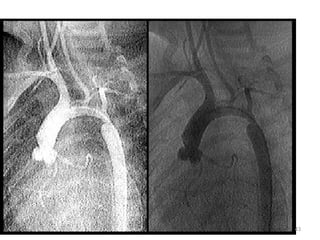

Acyanotic CHD… 2.3 Coarctationof the Aorta • Occur at any site from the arch of aorta to iliac bifurcation • 98% juxta ductal Pathogenesis • In utero arch hypoplasia Rt heart output passes through the ductus 38

• 39.

Acyanotic CHD… Clinical Manifestation  Hypertension → mechanical obstruction → renal  Differential cyanosis → pink upper extr. → cyanosed lower extr.  Classic signs - Disparity in pulse & BP - Radio-femoral delay - Systolic M at LMSB & inter-scapular area 39

• 40.

Acyanotic CHD… Diagnosis - Clinical - CXR - cardiomegaly & pulm. congestion - Notching of ribs - ECG - Echocardiography Prognosis – Untreated cases succumb by 20-40 years Complications - CVA - I/E - Aneurysms Treatment - Medical - IV PGE1 in neonatal age - Surgery 40